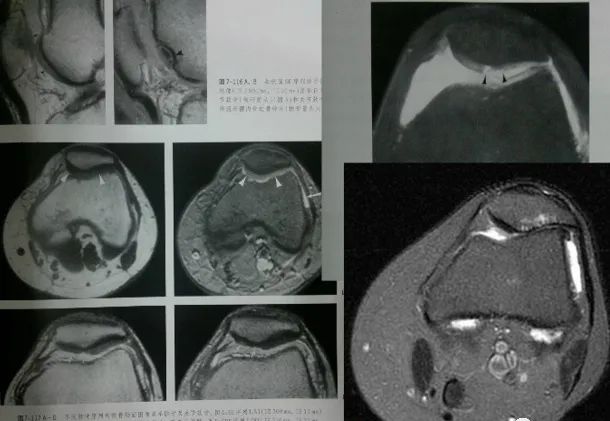

影像学检查

X线片:膝关节正、侧位及髌骨切线位

早期无异常;晚期可因软骨大部磨损,髌骨与股骨髁部间隙变窄、毛糙,关节对合不良,髌骨和股骨髁部边缘可有骨质增生。

• X线检查:髌骨切线位ⅹ线片对诊断髌趿排列乱及股骨髁发育不良具有十分重要的诊断价值,是髌骨软化症病因诊断常用方法。

• CT检查:对诊断髌股排列错乱及股骨髁发育不良有诊断价值,可作为X线片诊断的补充手段。其优点是能显示髌骨关节面病变及髌股关节间隙狭窄更清楚,也可以显示部分髌骨软骨病变。

• MRI检查:对髌骨软化症有较大的诊断价值,能够很好的显示关节积液、软骨退变及软骨下骨的囊性变等表现。

MR|判断髌骨软骨软化是以软骨内信号改变和软骨表面形态来诊断。病变可使髌骨软骨轮廓不同程度发生改变,表面毛糙,内部信号异常。

MRI表现局灶性低信号,T1T2加权像轻度轮廓改变,厚度变薄,软骨下有硬化的囊变

髌骨软骨软化症MRI表现:

0级:

A:SE序列T1加权像

B:SE序列T2加权像

C:STIR像

D:PGE序列T1加权像

Ⅰ级:

Ⅱ级:

Ⅲ级:

Ⅳ级: